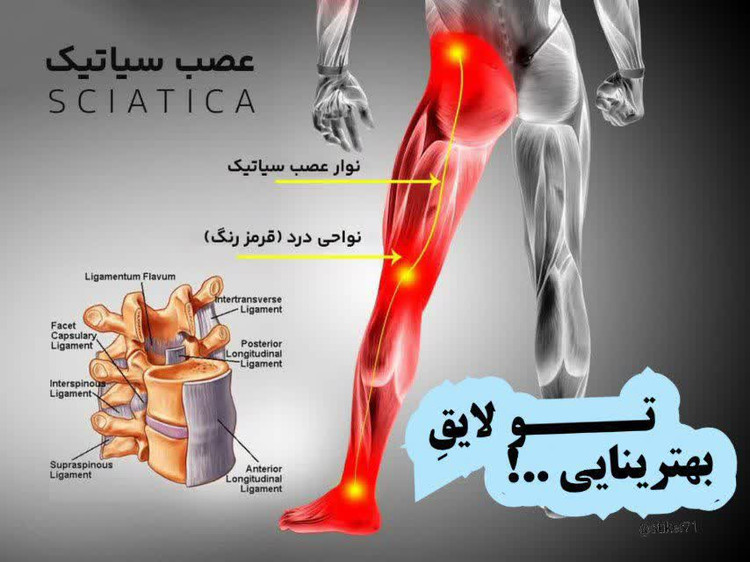

🦴 آرتروز گردن چیست؟

#آرتروز_گردن یا ساییدگی مهرههای گردن بهمرور زمان و بهدلیل افزایش سن، کار طولانی با موبایل، وضعیت بد نشستن و استرس ایجاد میشه. توی این حالت، غضروف بین مهرهها نازک میشه و باعث درد و خشکی میشه.

❗ علائم شایع آرتروز گردن:

✔️درد و خشکی گردن (بهخصوص صبحها)

✔️درد تیرکشنده به شانه، دست یا بازو

✔️سردردهای پشتسری

✔️سرگیجه یا گزگز دستها

✔️محدود شدن چرخش گردن

⚠️ چه چیزهایی آرتروز گردن رو بدتر میکنه؟

✳️استفاده زیاد از موبایل و خم بودن سر

✳️بالش نامناسب

✳️استرس و گرفتگی عضلات

✳️نشستن طولانی بدون حرکت